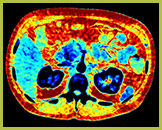

Выполните просмотр требуемой области с помощью нескольких решений благодаря эксклюзивному приложению Spectral Magic Glass для вычленения данных о составе тканей.

Здесь представлена серия изображений, на которых значения воксела обозначают эффективное атомное число. Эффективное атомное число может быть дробным, обозначающим какой-либо элемент, соединение или смесь. Данное число может отличаться от порядкового номера, указанного в периодической таблице. Единица для обозначения — Z.